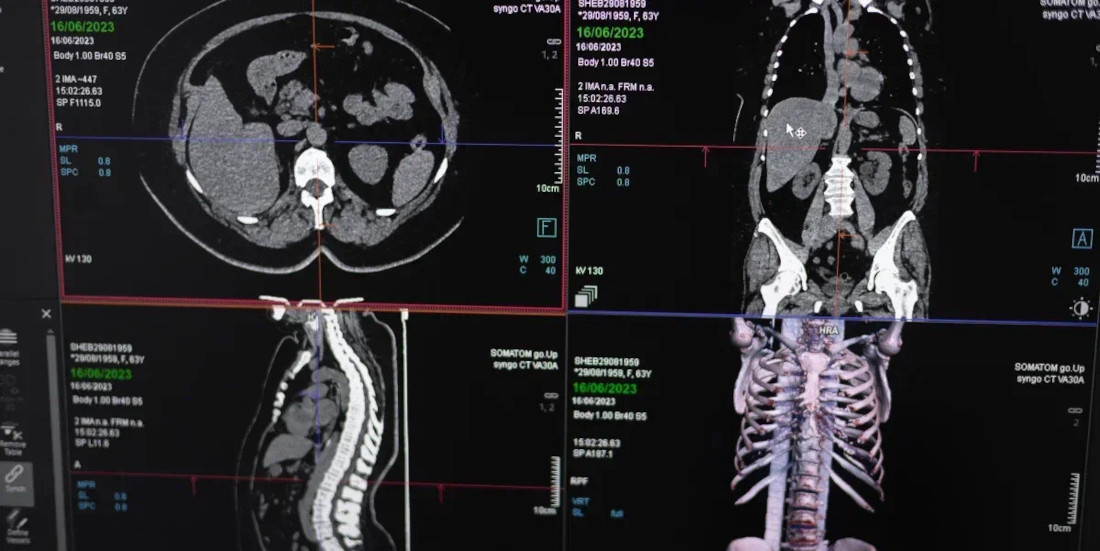

Компьютерная томография (КТ) — это современный высокоинформативный метод диагностики, основанный на использовании рентгеновских лучей. Он позволяет получать детальные изображения внутренних органов и структур организма в различных проекциях без инвазивных вмешательств. Метод применяется для выявления патологий на ранних стадиях и контроля эффективности лечения. Время проведения процедуры составляет всего несколько минут, что обеспечивает комфорт и безопасность пациента.

Область применения метода огромна. С помощью КТ можно выявить:

- Инсульт и внутренние кровоизлияния

- Ишемическую болезнь сердца и аневризмы сосудов

- Воспалительные процессы, такие как абсцессы и пневмония

- Доброкачественные образования — полипы, кисты, опухоли

- Онкологические заболевания — рак легких, молочной железы, предстательной железы и другие

- Переломы, травмы и повреждения костей и тканей

- Внутренние кровотечения

- Анатомические аномалии и изменения в органах